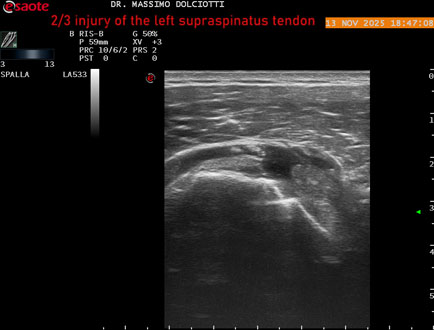

Data inserimento: 18/11/2025

Ecografia del: 13/11/2025

Strumento: Esaote MyLab Eight

Sonda: Lineare Multifrequenza 3-13 MHz

Età Paziente: M 58 anni

Motivazione dell'esame: da 4-5 mesi dolore alla spalla sinistra.

Commento all'esame: le immagini ed il video documentano il tendine sovraspinato sinistro disomogeneo per evidenza, in sede mediale sottobursale, di area ipoecogena di 4,5 mm per uno spessore di 3,3 mm, da ricondurre a lesione parziale che interessa i 2/3 del tendine.

Conclusioni: lesione 2/3 del tendine sovraspinato sinistro (2/3 injury of the left supraspinatus tendon).